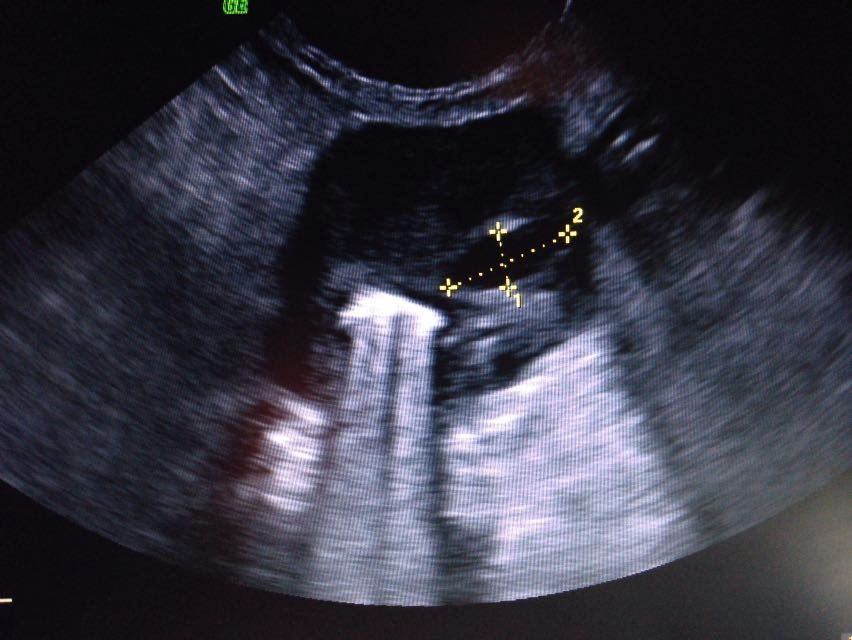

Ecografías

La ecografía veterinaria es un método de diagnóstico que se realiza con frecuencia en la clínica, sin que suponga un gran estrés para su mascota al ser una prueba diagnóstica no invasiva.

Al igual que en la medicina humana es ampliamente utilizada en el aparato reproductor de perras, gatas y pequeños mamíferos, y para explorar correctamente algunas vísceras, como el hígado o los riñones.

Este método complementa perfectamente otros diagnósticos como la radiografía o la endoscopia.